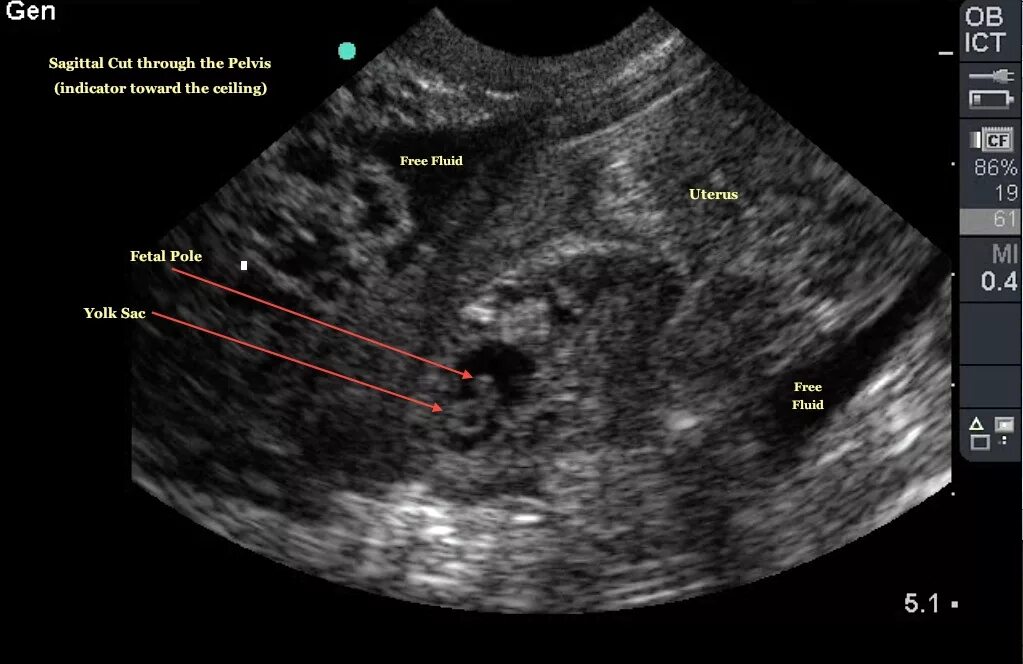

Можно ли на узи увидеть внематочную беременность